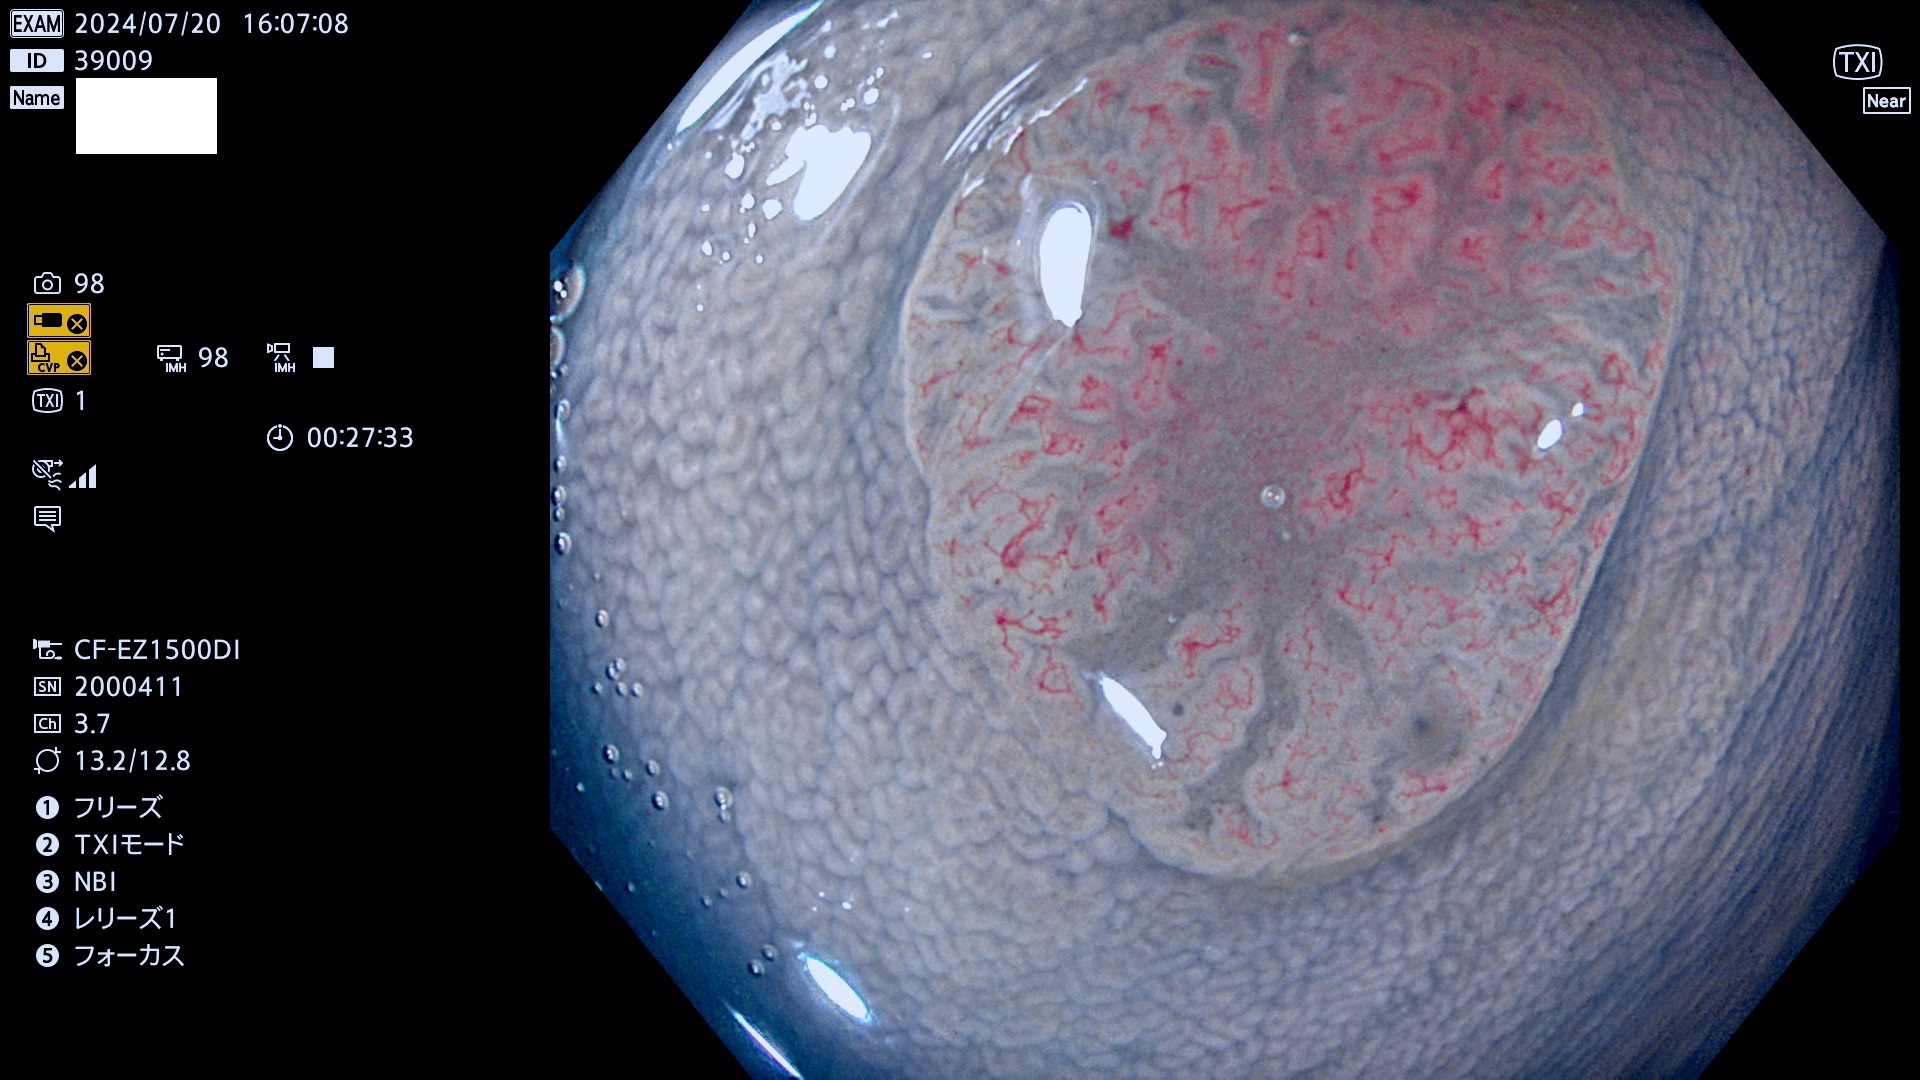

今週のUb、Uc型腺腫

完全に平坦な物をUb、陥凹している物をUcと呼びます。最も発見が難しく危険な病変です。

毎週の検査(木・金・土・日)に発見されたUb、Uc型・腺腫を、その週の日曜の夜にUPし1週間、提示します。

抽出の対象期間 2024年7月18日〜7月21の4日間(25件の検査)6件 (6/25=24%)